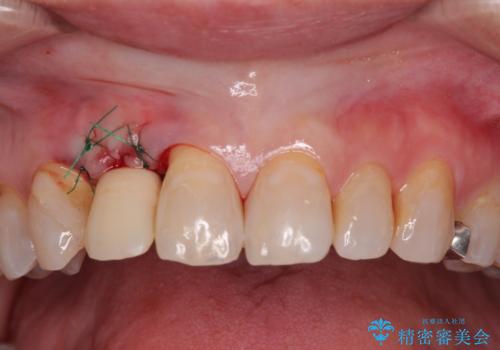

仮歯を事前に用意し、インプラント埋入時に即日で仮歯を装着する、即時荷重インプラントの計画で治療を進めて行くこととしました。

新幹線や飛行機を利用しても来院であり、極力来院回数を減らしたり、東京に用事があるタイミングに合わせてアポイントを調整したりと、負担が少なくなるようにして治療を進めて行きました。

来院間隔があいたため、予定よりも長くなりましたが、大きなトラブルもなく、外科処置は1回のみ、最小の来院数で無事に治療を終えることができました。